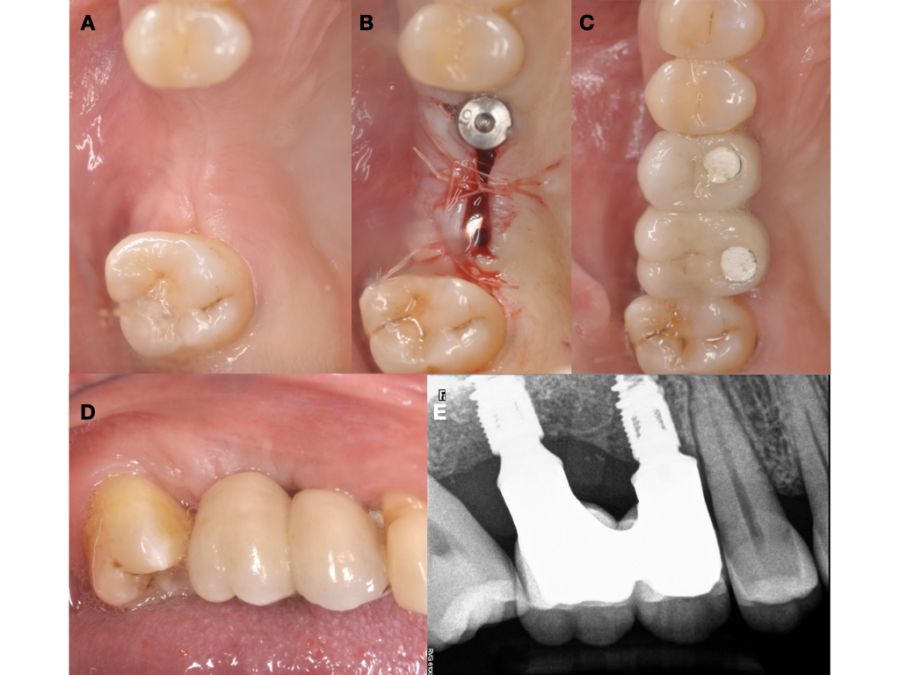

Seis meses tras la cirugía de elevación de seno maxilar se realizó la reentrada para la colocación de implantes. Se obtuvo una biopsia de tejido óseo de 3 x 7 mm mediante trefina y se solicitó un análisis histomorfométrico, obteniendo un 30,56% de hueso vital (Figura 7). Tras la muestra para la biopsia se colocaron dos implantes bone level Naturactis de ETK® (ETK Implants S.L, Sant Boi de Llobregat, España) con un torque de inserción de 35 Ncm, comprobándose su correcta colocación en el postoperatorio inmediato mediante una radiografía periapical (Figura 8). Seis meses tras la colocación de los implantes la paciente pudo acudir a realizarse la segunda fase para colocar pilares de cicatrización, y mediante un CBCT de comprobación se valoró la altura ósea final, teniendo un incremento de 4,2 mm en la zona del 1.6, y de 6,1 mm en la zona del 1.7 (Figura 9).

Quince días después de la segunda fase se realizó la toma de impresiones para la realización de dos coronas ferulizadas cemento-atornilladas sobre bases de titanio, comprobándose el ajuste mediante una radiografía periapical paralelizada (Figura 11). Seis meses tras la colocación de la restauración se realizó una revisión clínica y radiográfica, observando el buen aspecto de los tejidos blandos (Figura 12).